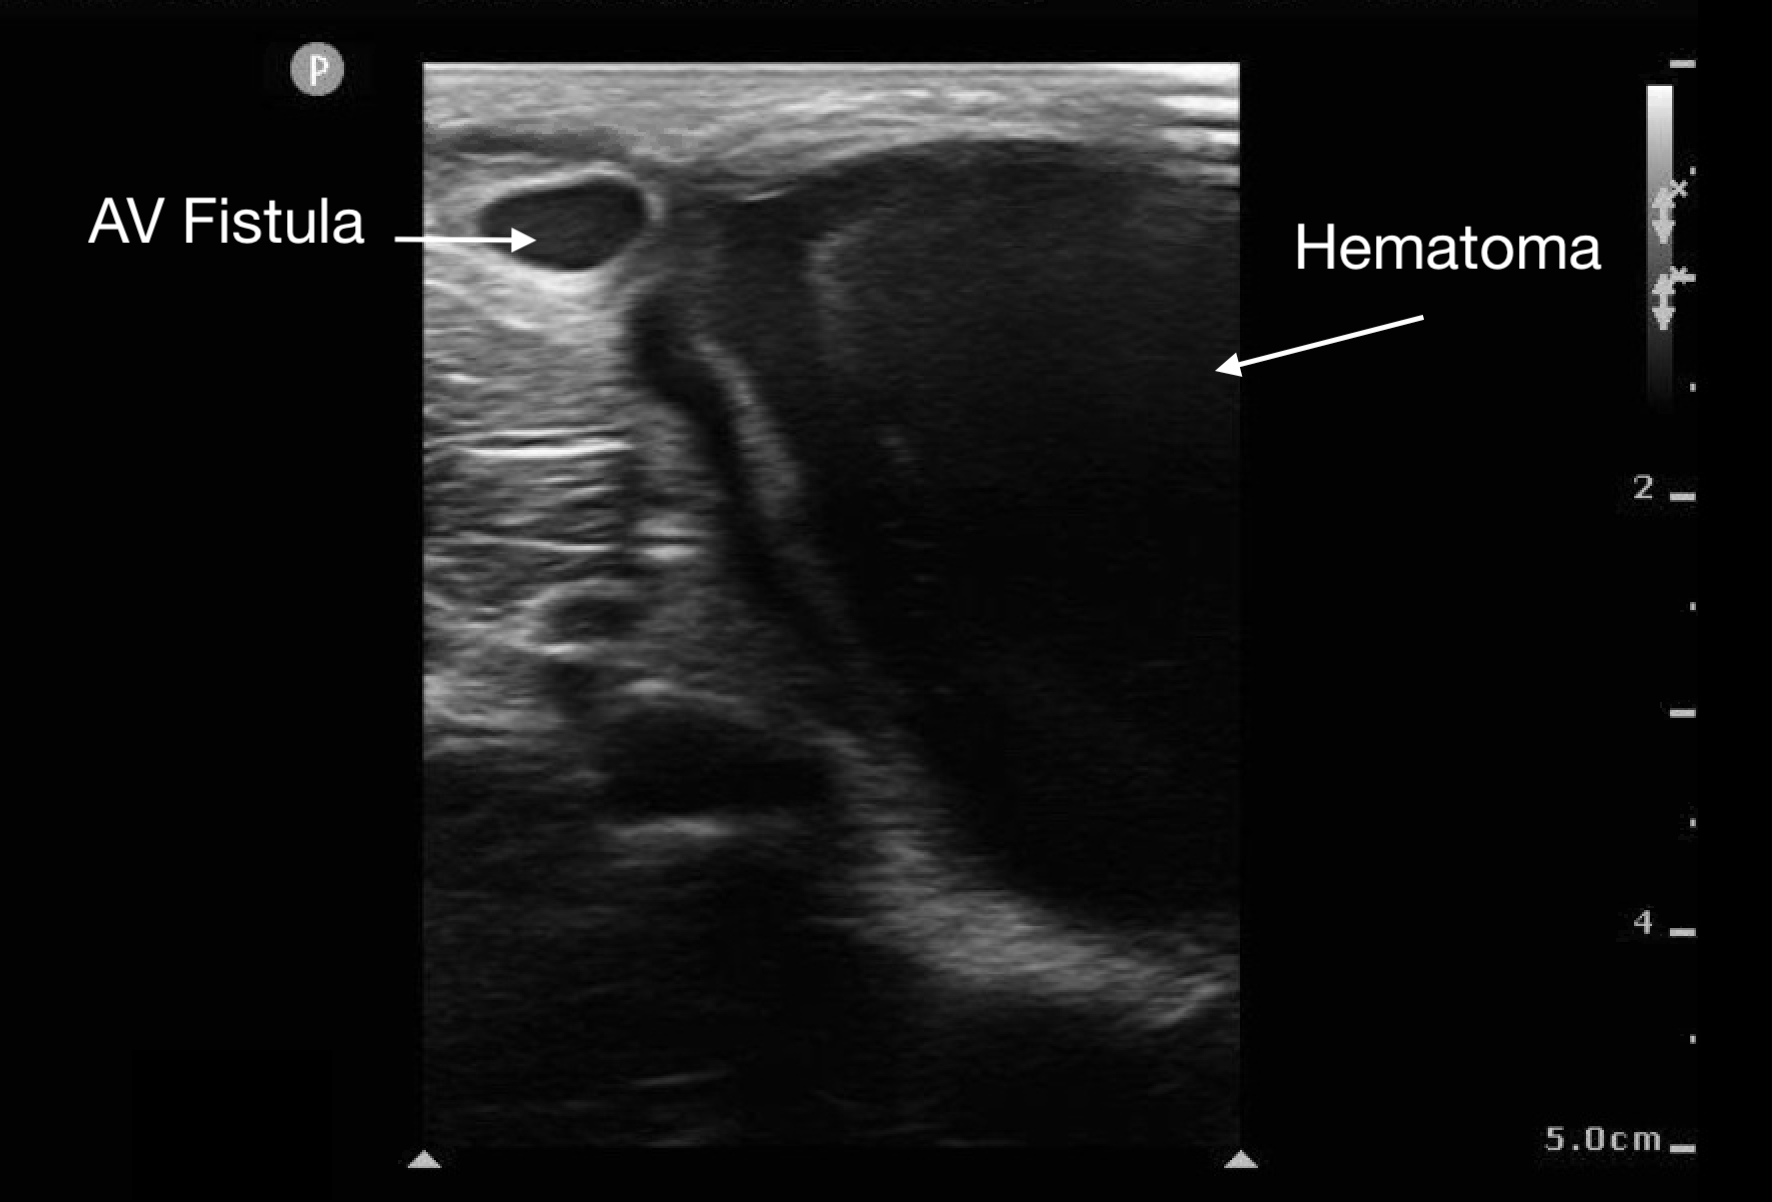

Soft Tissue

Abscesses and hematomas are readily identifiable on ultrasound as abnormal fluid collections in areas of tenderness or swelling. The appearance of the fluid varies depending on its contents, the presence of gas, and the clotting state of the hematoma. Fluid may appear anechoic (most common), heterogeneous, or even isoechoic. A key indicator in uncertain cases is the posterior acoustic enhancement generated by the fluid contents.

Figure 10.

Superficial abscess with posterior acoustic enhancement and surrounding cobblestoning (from cellulitis) deep to the abscess.

Figure 11.

Large hematoma from ruptured AV fistula seen in upper left corner of image.

Before draining an abscess, it is crucial to use color Doppler to rule out a pseudoaneurysm or nearby large vessels. This step helps prevent inadvertent incision into a vascular soft tissue structure, such as a lymph node, which may appear similar to an abscess.